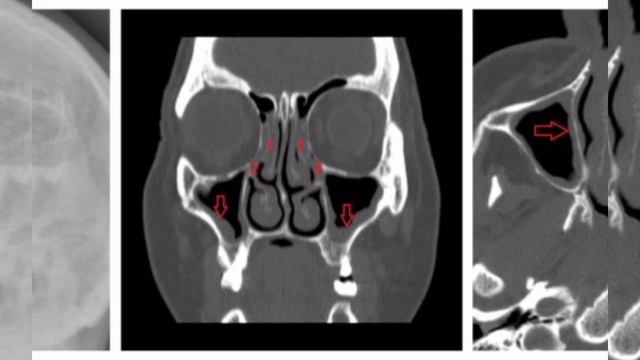

Слизистая ппн

Слизистая ппн 113 фото